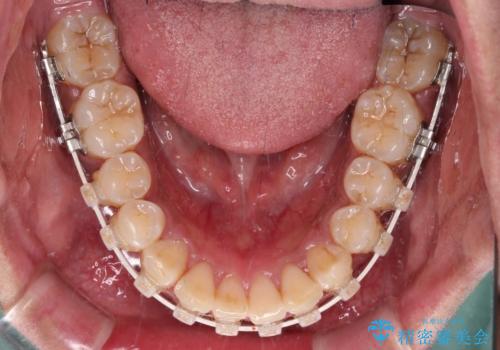

- 審美装置

- 2年2ヶ月

- 10-30回

口元の突出感はあまりありませんでしたが、上顎歯列が全体的に前方にあり、更には下顎歯列が深く咬みこんでいるために、上顎前歯が前方に突出している状態でした。

抜歯は行わず、補助装置を用いて上顎歯列全体を後方移動させ、ワイヤー装置にて奥歯の咬み合わせを改善していくこととしました。